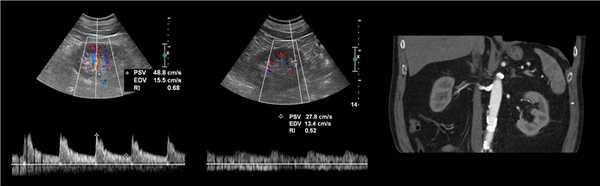

Рисунок. Пациент с острой почечной недостаточностью и рефрактерной артериальной гипертензией. УЗИ брюшной аорты и почечной артерий затруднено из-за газа в кишечнике. На сегментарных артериях слева RI о,68 (1), справа RI 0,52 (2), разница 0,16. Спектр правой сегментарной артерии имеет форму tardus-parvus — время ускорения увеличено, PSV низкий, вершина округлая. Заключение: Косвенные признаки стеноза правой почечной артерии. КТ-ангиография подтвердила диагноз: в устье правой почечной артерии атеросклеротические бляшки с кальцификацией, стеноз умеренной степени.